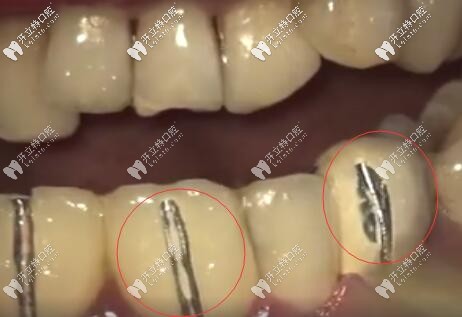

因?yàn)槌霈F(xiàn)牙齦黑線也說明烤瓷牙牙冠與牙根之間不密合,已經(jīng)有一條縫了,有了這條縫,食物殘?jiān)?、?xì)菌等都容易從這條縫進(jìn)入牙套里去。

從而讓里面的基牙發(fā)生齲壞,時(shí)間久了,這個(gè)牙就整個(gè)爛掉了,有些醫(yī)生技術(shù)不過比如備牙,粘結(jié),牙冠做的不合適,與牙根牙齦不密合,挺不過幾年都有可能出問題。

烤瓷牙尤其那種連著做的連橋冠太多的,兩端基牙承受不住咬合,長(zhǎng)時(shí)間就會(huì)有縫隙,很容易導(dǎo)致基牙齲壞。

烤瓷牙會(huì)刺激牙齦,導(dǎo)致牙齦萎縮,牙冠與基牙不貼合,建議大家要做也做全瓷牙,基牙齲壞幾率會(huì)小一些。